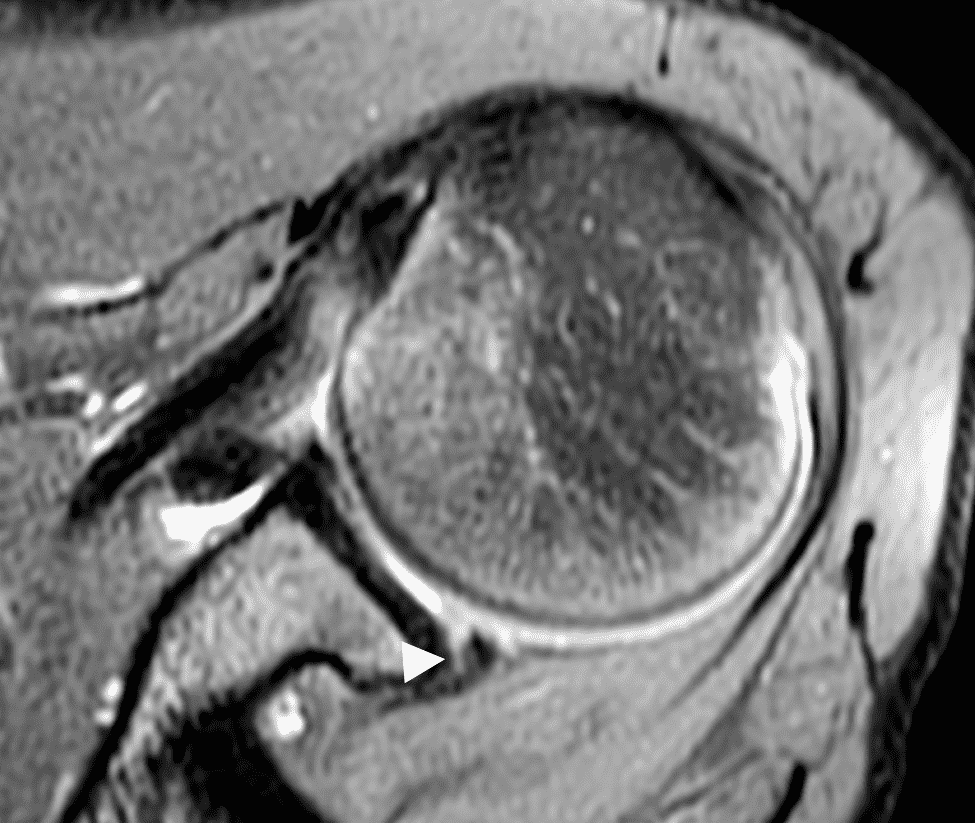

Figure 5: 16-year-old male high school baseball player with acute left shoulder batting injury. (5A – 5C) Axial T2-weighted fat-suppressed images demonstrate findings of posterior instability injury including a nondisplaced posterior chondrolabral junction tear (Kim-type lesion, arrowhead), complete posteroinferior chondrolabral junction and capsular tearing (solid arrows), and anteromedial humeral head impaction fracture (dashed arrow).